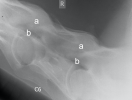

5. – 7. Halswirbel

Sehr leichtgradige Einengung des Austrittsloches der Nerven (b). Die Facettengelenke sind schön glatt ausgebildet.